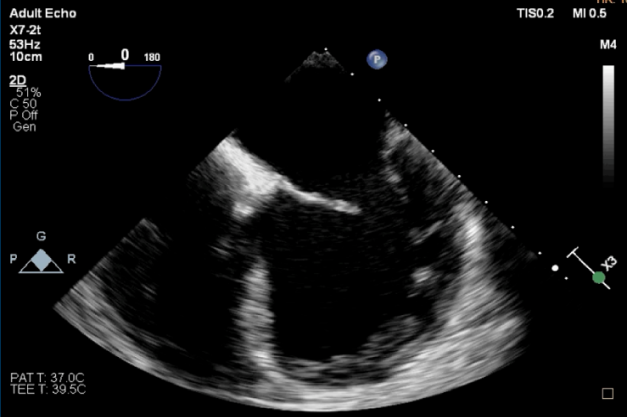

术前TEE

TEE短轴脱垂区域显示(P2、P3区大范围脱垂)

TEE短轴脱垂区域显示(color,血流来源于P2、P3区)